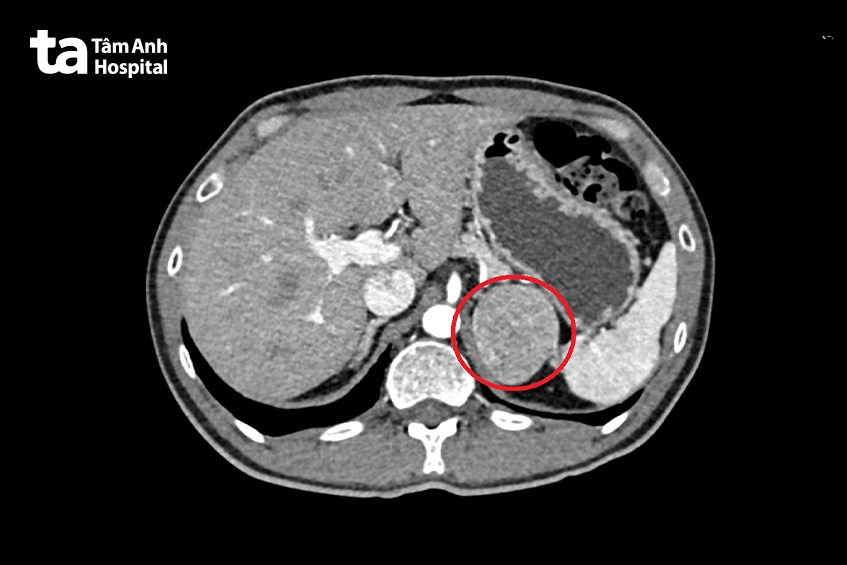

Tháng 10/2023, anh P. được vợ khuyên tới BVĐK Tâm Anh TP.HCM. Với triệu chứng kể trên, bác sĩ CKI Võ Trần Nguyên Duy, khoa Nội tiết – Đái tháo đường, BVĐK Tâm Anh TP.HCM nghi ngờ người bệnh gặp vấn đề ở tuyến thượng thận. Đúng như dự đoán, kết quả siêu âm bụng phát hiện tuyến thượng thận trái có u lớn. Người bệnh tiếp tục được chụp CT (chụp cắt lớp vi tính), xét nghiệm máu và nước tiểu, đã “định vị” chính xác u tủy thượng thận trái hiếm gặp, 8/1.000.000 người mắc bệnh. Khối u nằm trong lõi tuyến thượng thận, phát triển lớn đẩy và đè lên dạ dày, bó mạch lách.

Không chỉ vậy, khối u kích thước lớn có nhiều mạch máu tăng sinh xung quanh, nằm sâu vùng sau phúc mạc, bao quanh là các tạng như: thận, lách, tụy, ruột và các mạch máu lớn. Vì vậy, ekip phẫu thuật đánh giá cặn kẽ nguy cơ chảy máu, khó cầm máu và tổn thương các cơ quan lân cận. Các bác sĩ khoa Tiết niệu quyết định phẫu thuật nội soi cắt bỏ khối u tủy thượng thận nhằm giảm thiểu xâm lấn, giảm đau cũng như giúp người bệnh phục hồi nhanh hơn.